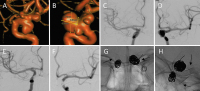

Neurovaskuläre Therapieoptionen bei komplexen Aneurysmen der Arteria carotis interna // Neurovascular therapeutic options in complex intracranial aneurysms

Journal für Neurologie, Neurochirurgie und Psychiatrie 2021; 22 (3): 128-134 Volltext (PDF) Summary Praxisrelevanz Abbildungen